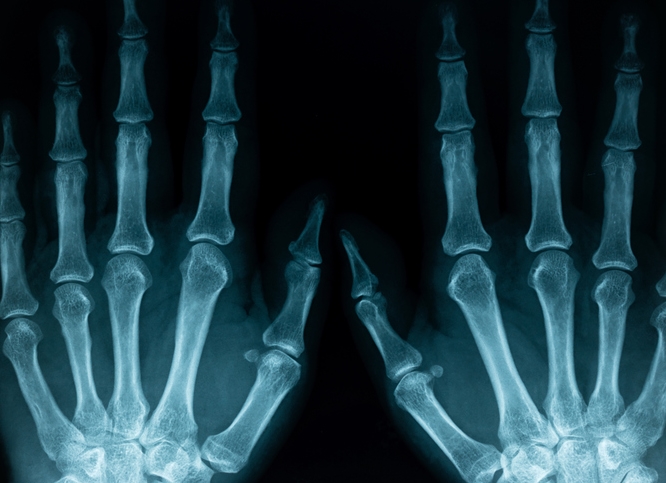

손가락 마디 통증 병원 선택은 증상에 따라 달라요. 일반적인 통증이나 외상성 문제는 정형외과, 면역 관련 문제로 의심된다면 류마티스내과를 방문하시는 게 좋아요. 엑스레이, 초음파, 혈액검사 등을 통해 원인을 정확하게 분석할 수 있습니다.